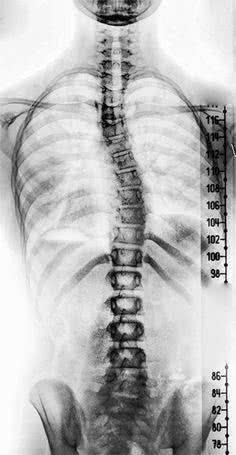

Tłumacząc to Paulowi, ortopeda przyglądał się zdjęciu rentgenowskiemu jego kolan. - Od razu widziałem, że nie wyglądają najlepiej - stwierdza Paul. - Pierwszą rzeczą, jaką mi powiedział lekarz, było to, że ma wrażenie, że patrzy na kolana siedemdziesięcio- lub osiemdziesięciolatka.